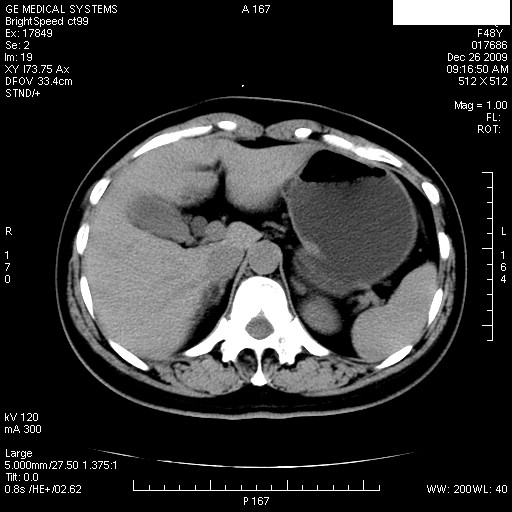

患者女性 48岁 突发上腹部疼痛,无其他不适,查体莫菲氏征阴性,ct示:胆囊炎,胆总管上端轻度扩张

图片如下:

1.图像看上去不是同一人(前组图像十二指肠未见明显异常,后组图像可见十二指肠占位)

2.后组图象印像

a.十二指肠球部前壁占位

b.坏蛆性胆囊炎,胆囊-结肠瘘(瘘口微小且时间较短,结肠内容返流入胆囊,形成胆囊壁钙化,胆囊内钙盐等沉积)

c.胆管炎,肝外胆管轻度扩张